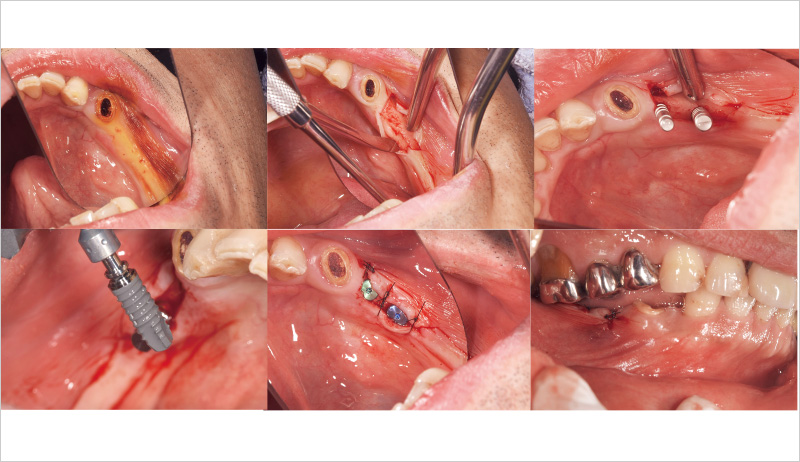

この症例が私にとって初めてのSPIインプラント症例だった。ドリルキットがとても簡便で操作性も良く感じた。こちらの症例は初心者でもできる症例を挙げているので参考にしていただけたらと思う(図16~19)。

まずフラップを開く前にヨード染色を行い、付着歯肉の幅を確認する。その後、フラップを全層弁で開く(私の場合はそこまで大きくは開けないことが多い)。床形成を行い平行指示ピンを入れ平行性を確認。SPIイニセルインプラントをコンディショニングした状態で埋入の準備を行う。₅:φ4.0長さ11mm、 ₆:φ4.5長さ11mmのSPIイニセルインプラント エレメントRCを埋入。付着歯肉を減らさないように縫合を行った。

![[写真] オペ中の写真](/academic/dentalmagazine/wp-content/uploads/sites/2/2025/09/194-8_photo16.jpg)

図16 オペ中の写真。本症例が初めてのSPIインプラント症例だった。 -